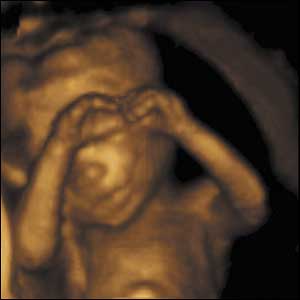

15 weeks gestation, 11cm crown to rump

5 of 10

This baby's brain has developed sufficiently to enable him apparently to sense the other parts of his body. He can bring his fingertips together so they touch.